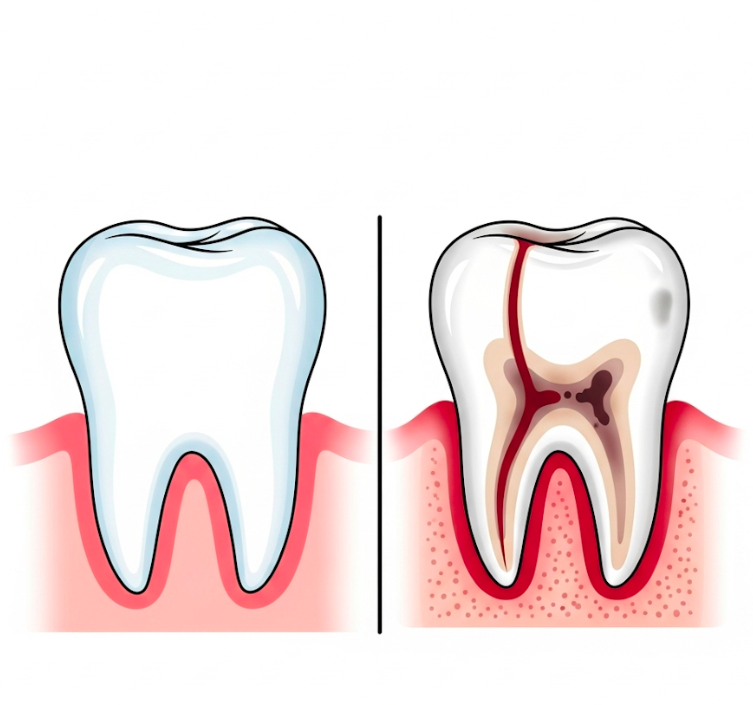

Czy zdarzyło Ci się poczuć nagły, ostry ból przy nagryzaniu...

Ten ból zęba nie daje Ci spać? Pozwól, że...